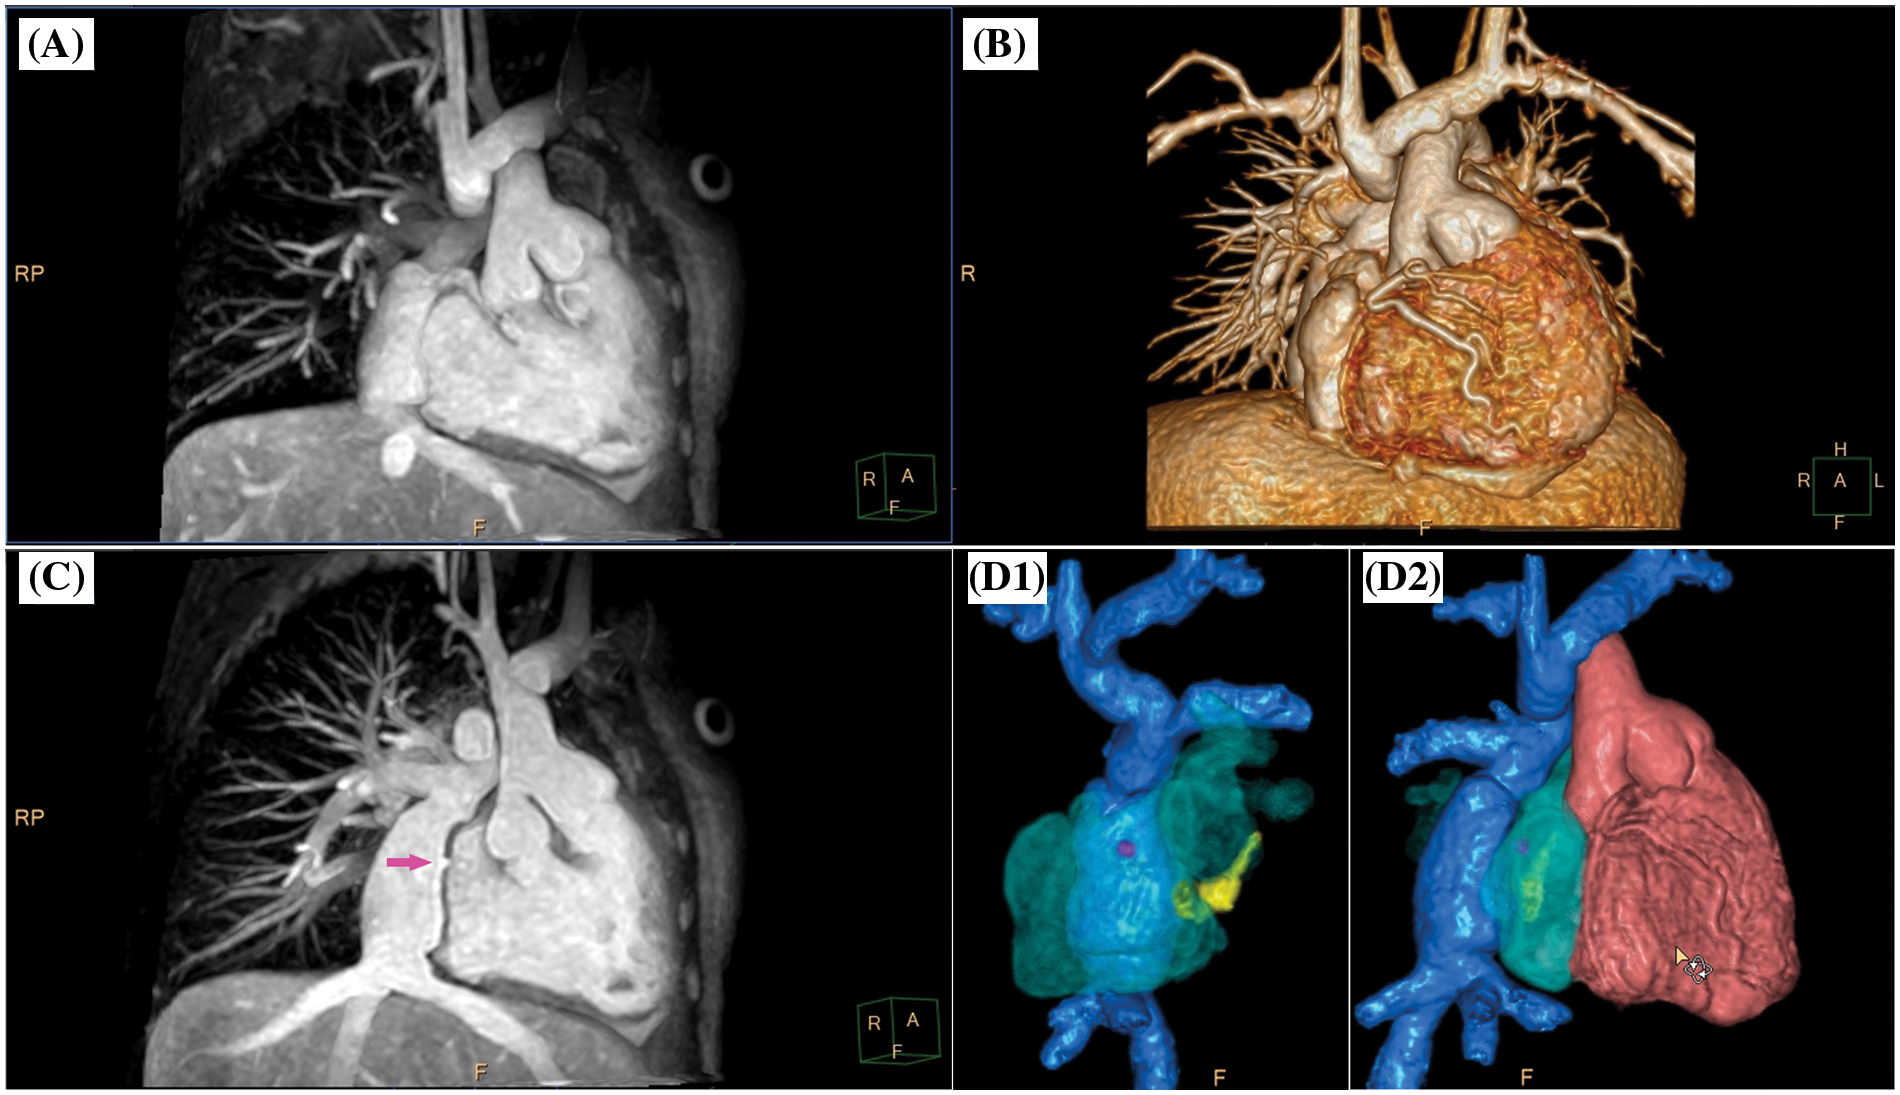

CMR imaging is often requested prior to interventional or surgical treatment when three-dimensional segmentation of the cardiac and vascular cavities is needed for preprocedural planning and peri-procedural guidance [5,17]. Especially in patients with congenital heart disease, detailed anatomical assessment of all cardiac and vascular structures is crucial for therapeutical decision making and interventional assistance (Figs. 3–5, Video S1–S3). At present, contrast-enhanced 3D dynamic MR angiography represents the widely accepted standard for the evaluation of the thoracic vessels in children [2]. However, the timing of image acquisition needs to be designed for the clinical question and depiction of vascular structures is invariably limited to the targeted circulation. The present study corroborated a significant SIR decrease together with a limited anatomical assessability of vascular structures in the non-targeted circulation for conventional 3D MR angiography. When aiming at the anatomical assessment of both, the pulmonary and systemic circulation, 4D MR angiography could be used instead. The most important benefit of the 4D technique relies on the inherent temporal resolution, enabling the assessment of dynamic flow conditions in the observed vascular region. However, the present study data showed that the advantage of a time-resolved MR angiography went at the expense of an overall reduced SIR when compared to 3D angiography which confirmed former study data reporting a decreased image quality of 4D angiography [18]. An additional disadvantage of contrast-enhanced dynamic MR angiography for evaluation of CHD patients relates to the usually ECG untriggered acquisition being designed for extracardiac vessel depiction and, thus, being less suitable for intracardiac morphology evaluation [19].

Figure 5: Clinical case example III. (A) Animated angulated volume-intensity projection of the nsWHcs dataset; (B) composite volumetric surface rendering of vascular compartments/endoluminal cavities including inferior vena cava and bilateral Glenn anatomy (blue), atria/single ventricle (violet), ascending aorta (transparent violet) and tricuspid annulus/rudimentary right-ventricular cavity (brown); (C) multiplanar-reformatted projectional view of bilateral Glenn anatomy (angulated coronal geometry); (D) cine imaging of an adjusted 4-chamber geometry depicting tricuspid valve/right-ventricular cavity. Please refer to video 3 for a fully animated case presentation

Video 3 (.MP4 file)

Clinical case example III (same case as shown in Fig. 5)

A 5-year-old boy (bodyweight, 14 kg; heart rate, 85/min; propofol sedation) with a single ventricle (hypoplastic right heart syndrome) after bilateral bidirectional Glenn procedure was scheduled for radiofrequency ablation of an accessory pathway prior to finalizing staged palliative surgery leading to total cavopulmonary connection. Preinterventional CMR imaging identified “supero-inferior ventricle” anatomy with tricuspid annulus and contractile, rudimentary right-ventricular cavity [25]. On subsequent invasive electrophysiological testing, atriofascicular pathway tachycardia (“Mahaim”) was identified and successful radiofrequency ablation performed at the lateral tricuspid valve annulus and neighboring myocardium of the rudimentary right ventricle.